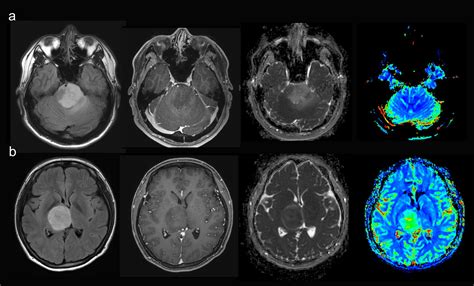

The journey toward a formal diagnosis usually begins with a neurological examination followed by advanced imaging. Physicians rely on several diagnostic tools to map the tumor’s size, location, and relationship to vital brain structures. Magnetic Resonance Imaging (MRI) with contrast remains the gold standard for visualizing these growths. In many cases, specialized sequences such as spectroscopy or perfusion imaging are used to differentiate between tumor tissue and postoperative changes.

• high grade glioma MRI